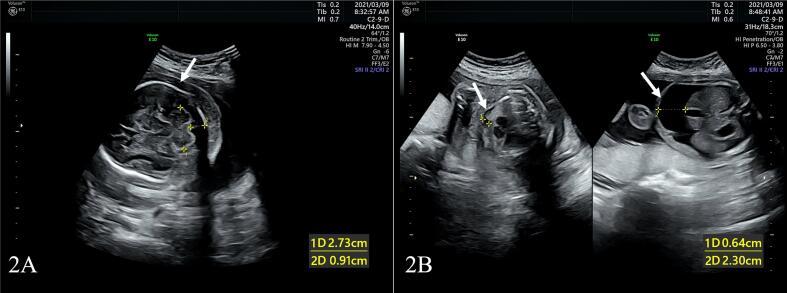

Non-immune hydrops fetalis (NIHF) is a common and severe manifestation of many genetic disorders. The ultrasound is an ideal method for diagnosing hydrops fetalis during pregnancy. Since most NIHFs do not have an identifiable cause, determining the underlying etiology remains a challenge for prenatal counseling. Due to advancements in exome sequencing, the diagnostic rates of NIHF have recently increased. As reported here, DNA was extracted from the amniotic fluid of a pregnant woman who was prenatally diagnosed with a NIHF type of unclear origin. Amniocentesis sampling demonstrated a normal female karyotype and copy number variation(CNVs) without alterations. Tri-whole exome sequencing (WES) was conducted to identify possible causative variants. In the fetus, a genetic mutation was identified as a homozygous form. The mutation was located on the glucuronidase beta (GUSB) gene: NM_000181.3: c.1324G > A; p. Ala442Thr; Chr7:65439349, which leads to mucopolysaccharidosis type VII. This mutation was inherited from the parents and was first reported to be related to NIHF. We conclude that the use of WES is beneficial for NIHF cases whose prognosis has not been explained by standard genetic testing.

非免疫性胎儿水肿(NIHF)是许多遗传疾病常见且严重的表现形式。超声检查是孕期诊断胎儿水肿的理想方法。由于大多数NIHF病例病因不明,确定潜在病因仍是产前咨询面临的挑战。随着外显子组测序技术的进步,NIHF的诊断率最近有所提高。在此报告中,从一名产前诊断为病因不明的NIHF类型的孕妇羊水中提取了DNA。羊水穿刺检查显示女性核型和拷贝数变异(CNV)均正常,无改变。进行三联全外显子组测序(WES)以鉴定可能的致病变异。在胎儿中,发现一个纯合形式的基因突变。该突变位于β-葡萄糖醛酸酶(GUSB)基因上:NM_000181.3:c.1324G>A;p.Ala442Thr;Chr7:65439349,导致VII型黏多糖贮积症。该突变由父母遗传而来,首次报道与NIHF相关。我们得出结论,对于标准基因检测无法解释预后的NIHF病例,使用WES是有益的。